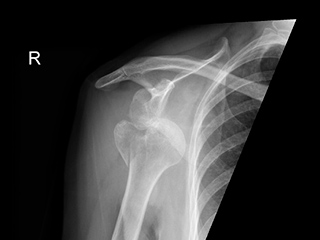

La fractura del húmero proximal se observa en todos los grupos de edad, pero son más frecuentes en los pacientes de edad avanzada representa un 5% de todas las fracturas y mas de 50% en las personas mayores de 60 años. En pacientes jóvenes se producen por traumatismos de alta energía.

Se clasifica según la estabilidad y el desplazamiento de los fragmentos:

- Tipo 1 de Neer: fractura con desplazamiento menor de 1 cm. o con angulacion menos de 45º.Son fracturas estables y casi siempre se trata conservador mediante vendajes funcionales o cabestrillos.

- Tipo 2 de Neer: fractura en 2 fragmentos sin desplazamiento de los fragmentos tuberositarios con riesgo de necrosis por la afectación vascular que se puede tratar de forma conservador o quirúrgico según el desplazamiento de los 2 fragmentos

- Tipo 3 de Neer: son las fracturas que afecta a la tuberosidad y tiene desplazamiento mayor de 1 cm. y angulacion de mayor de 45%.Son casi siempre quirúrgicas mediante técnicas de reducción abierta y fijación con placas o con agujas de kishner.

- Tipo 4 de Neer: son fracturas complejas en 4 fragmentos o fracturas que asocia luxación glenohumeral tiene alto riesgo de necrosis vascular de la cabeza y por eso en la mayoría de los casos si no se puede hacer una reconstrucción correcta de los fragmentos esta indicado la prótesis de hombro.